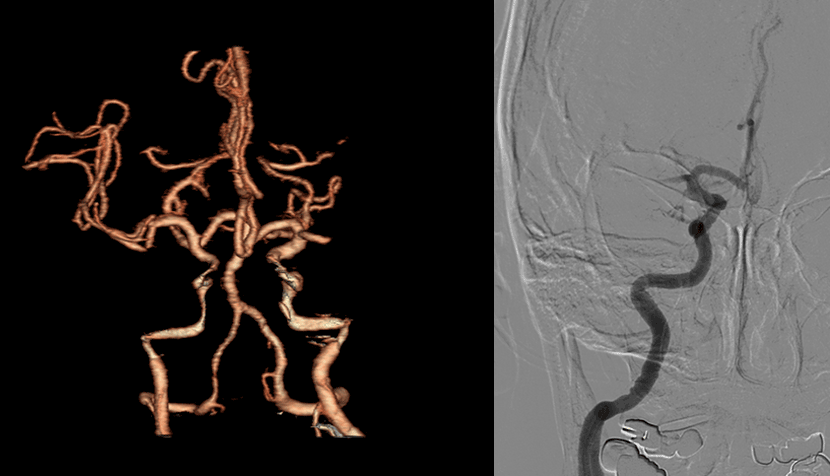

CT혈관 조영술과 뇌혈관조영술에서 좌측 중대뇌동맥의 폐색이 보임

혈관내 수술 기법으로 혈관안에 있는 혈전을 제거

수술전 사진과 비교시, 사라졌던 혈행이 되살아남